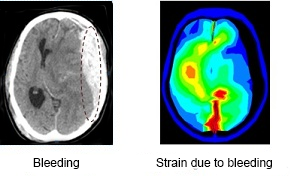

The figures below depict a preliminary result of the method. The left figure shows a cross-section of the patient brain with bleeding from the CT scan. The right figure shows the simulated deformation in color scale. The scale goes from blue (low deformation) to red (high deformation).